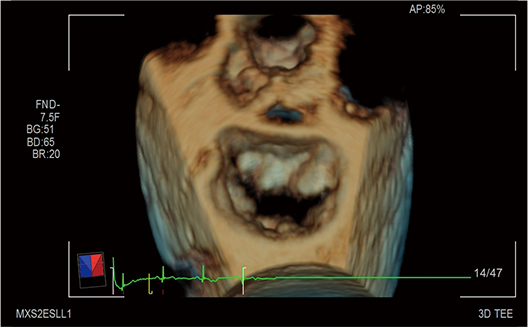

Cardiac 3D is becoming an indispensable part of the cardiac examination. Diagnostic information is attained at the next level for diagnosis and treatment in cardiac disease. The high quality product is achieved in all aspects of image quality, operability, and functionality.